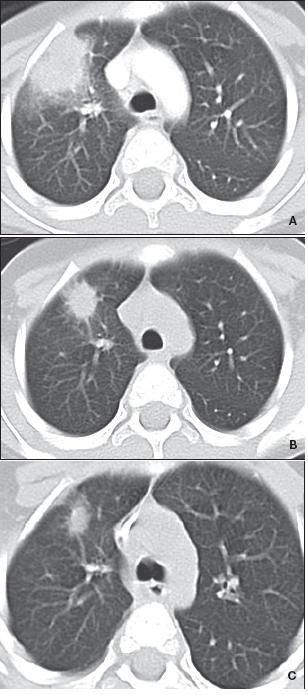

Chest radiographic findings are not sensitive for the diagnosis of invasive pulmonary aspergillosis, and radiographs have largely been replaced by chest CT scans. The most common radiographic findings are single or multiple nodules, wedge-shaped pleural-based infiltrates, and cavities (Figures 2 and 3). Diffuse infiltrates are rare.

The halo sign is the most suggestive sign of aspergillosis and is manifested by a macronodule (larger than 1 cm in diameter) surrounded by a perimeter of ground-glass opacity. It represents an area of angioinvasive aspergillosis with infarction and coagulative necrosis surrounded by alveolar hemorrhage. 16 This is a fleeting and early sign that may not be appreciated, particularly in nonneutropenic patients. Other fungal pathogens (Mucor, Scedosporium, and Fusarium) or bacteria (Pseudomonas aeruginosa) also may produce the halo sign.

Figure 2 – These CT scans are from a neutropenic patient who had invasive pulmonary aspergillosis. On presentation, the patient had fever and had been taking broad-spectrum antibiotics; the CT scan showed a mass-like infiltrate with a halo sign (A). Some improvement can be seen after the recovery of the white blood cell count and 2 weeks of voriconazole therapy (B). After 6 weeks of treatment, a CT scan showed persistent abnormality (C). At wedge resection, pathology showed septate hyphae.

The air crescent sign, caused by contracting infarcted tissue, often occurs at the time of recovery of the white blood cell count in neutropenic patients with invasive pulmonary aspergillosis.